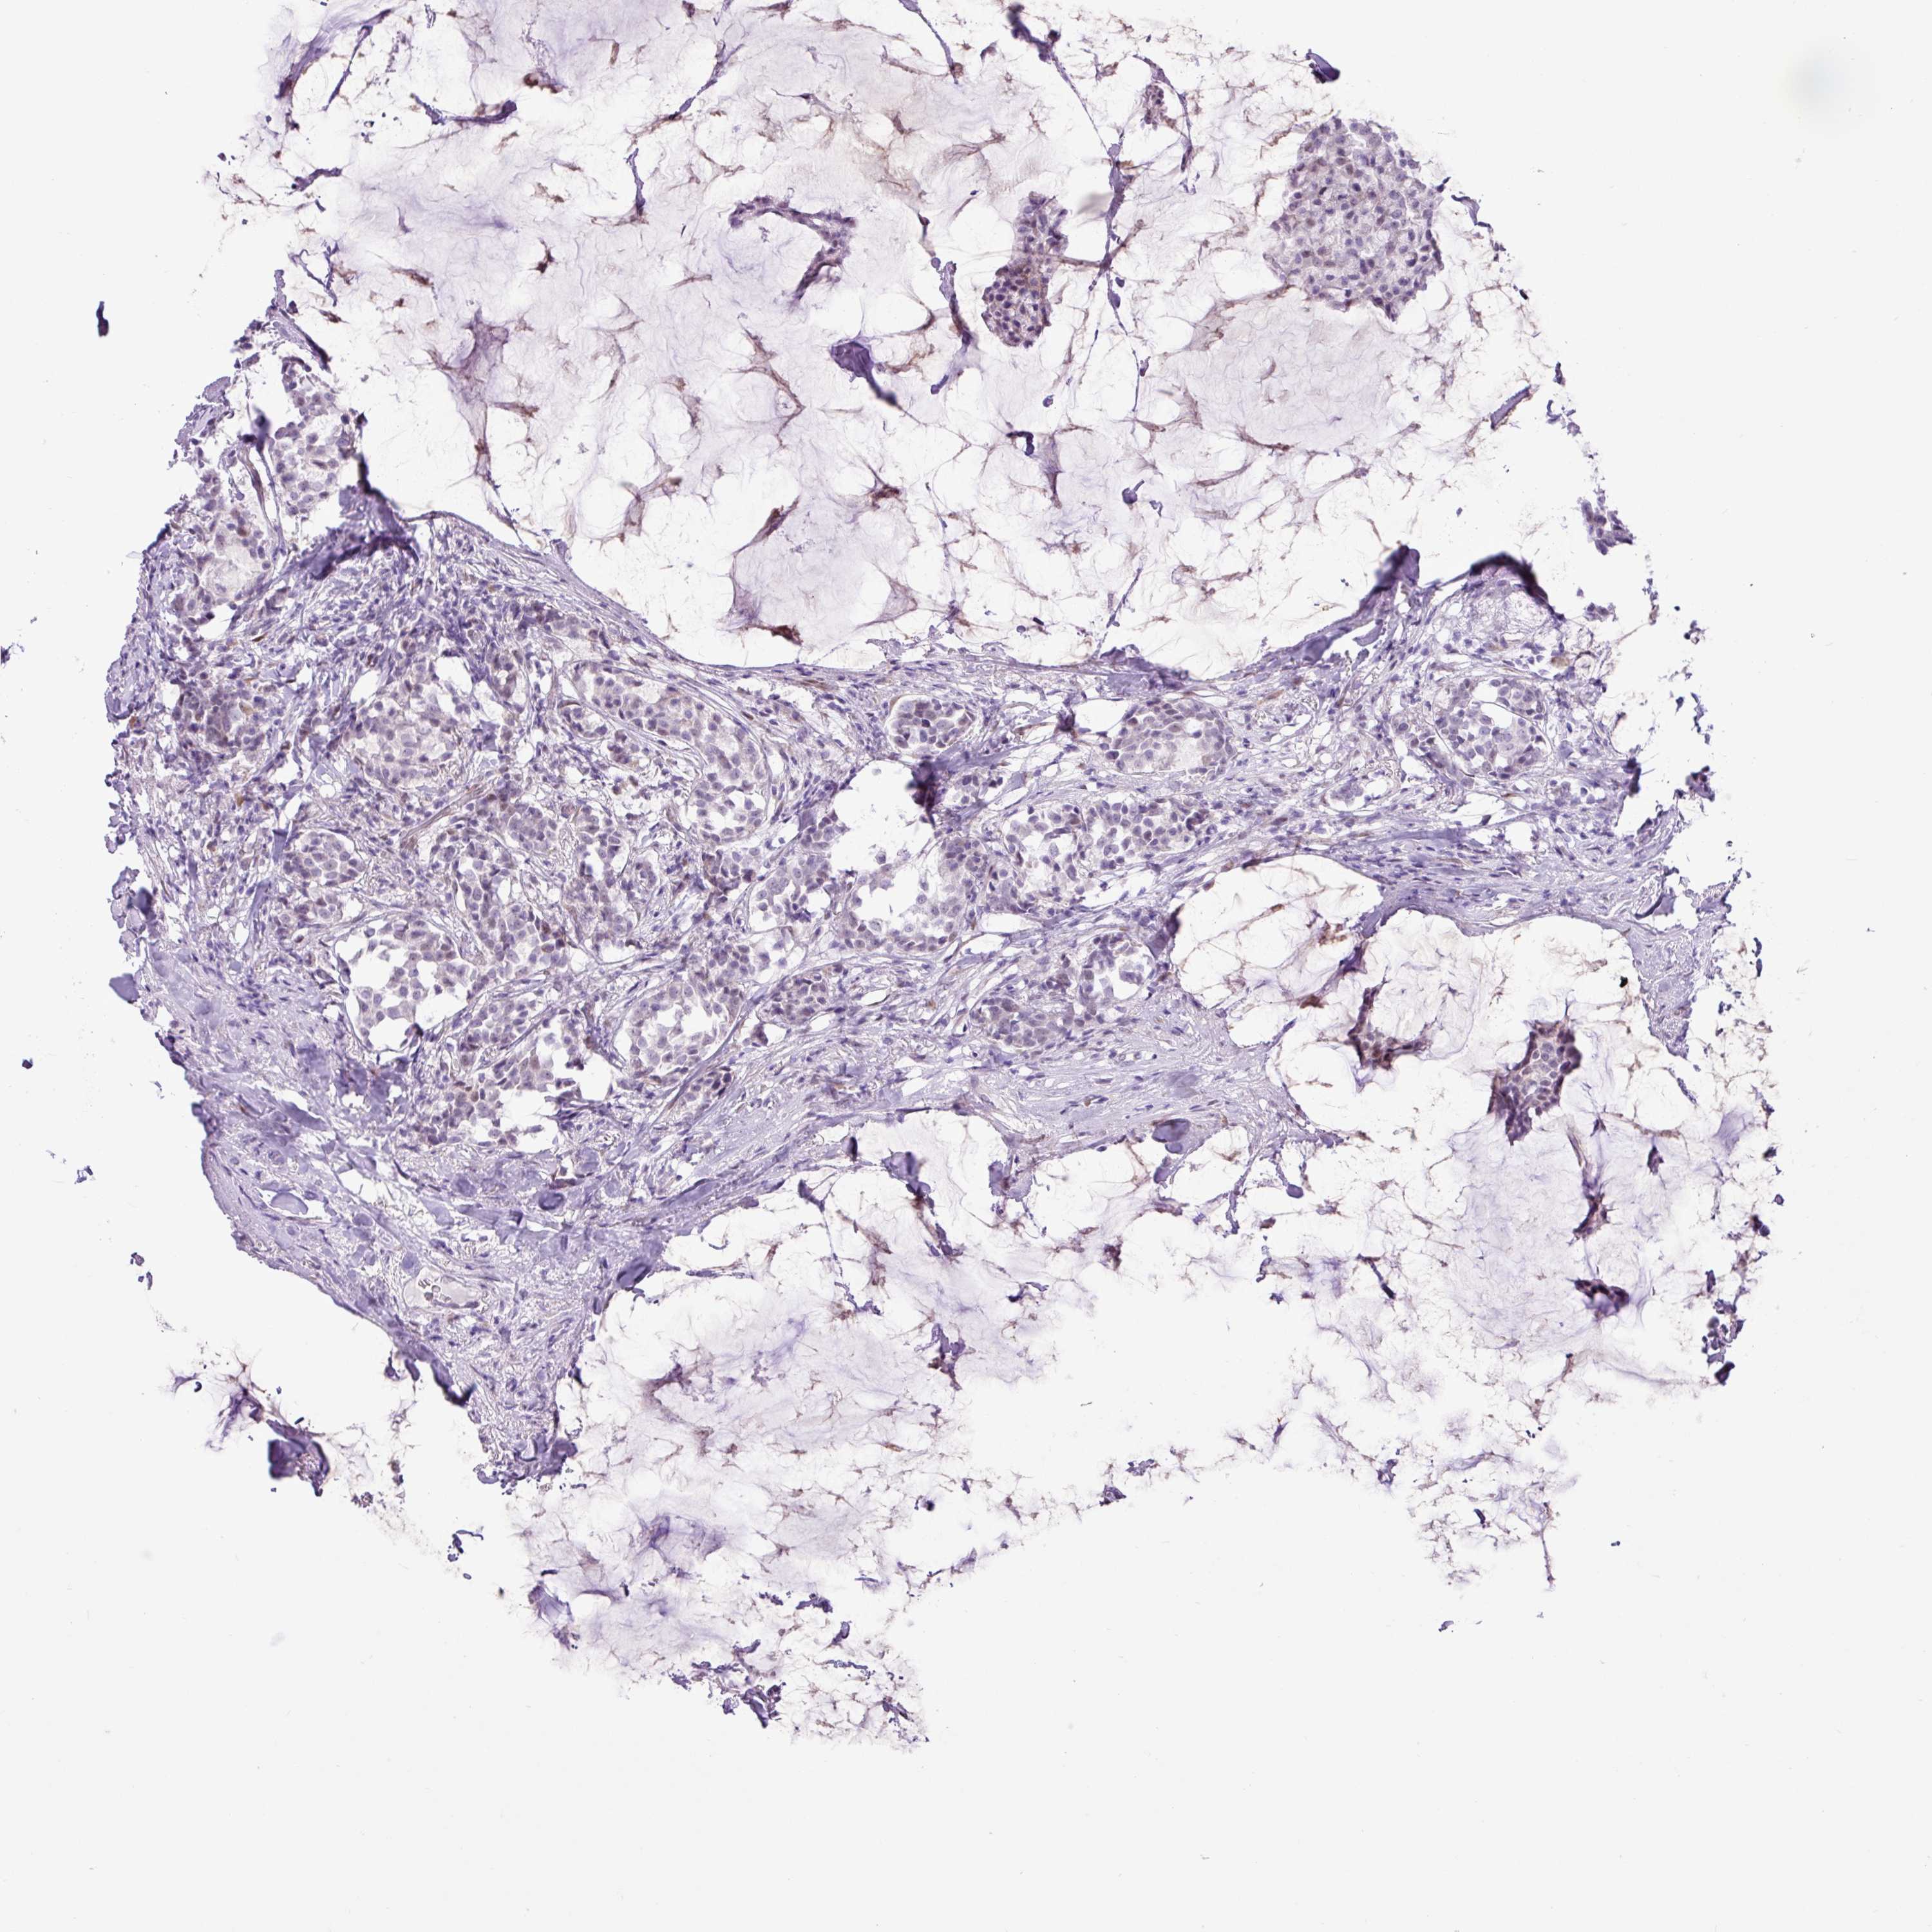

CANCER BREAST CANCER Show tissue menu

BRCA TCGA BRCA VALIDATION PROTEIN EXPRESSION

Breast cancer

Human cancer

ELOA2 is not prognostic in Breast Invasive Carcinoma (TCGA)